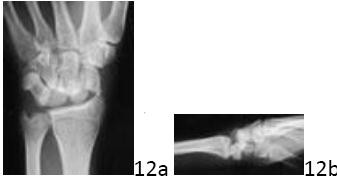

ORTHOPEDIC MCQS ONLINE HAND017 HAND AND WRIST SELF-SCORED EXAMINATION AAOS 2016 Question 1 of 100 Figures 1a …